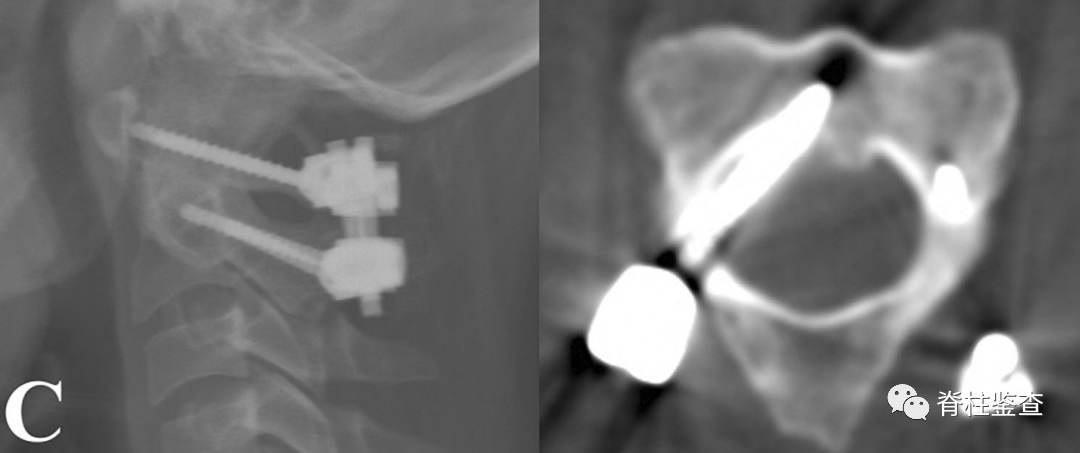

C:使用C2内侧开窗技术置入螺钉

D:尽管螺钉进入椎管,但未导致神经功能损伤案例二女性,29岁

C:通过C2内侧开窗技术技术进行C1-C2融合;术后神经功能完好,JOA评分17分